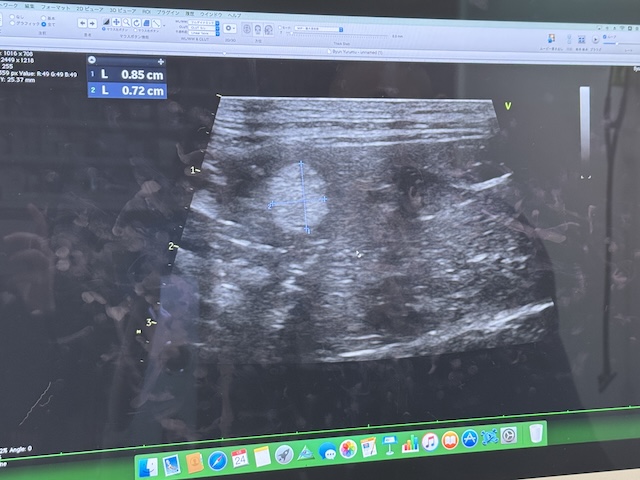

X선 검사랑 초음파 검사 결과를 들었습니다.

파일이 많아서 결과사진은 못받아서 문제가 있는 부분 사진만 찍었습니다.

비장에 혹이 있다 해서 ㅠ 한달 후에 크기 추적 검사를 해보기로 했습니다 ㅠㅠ